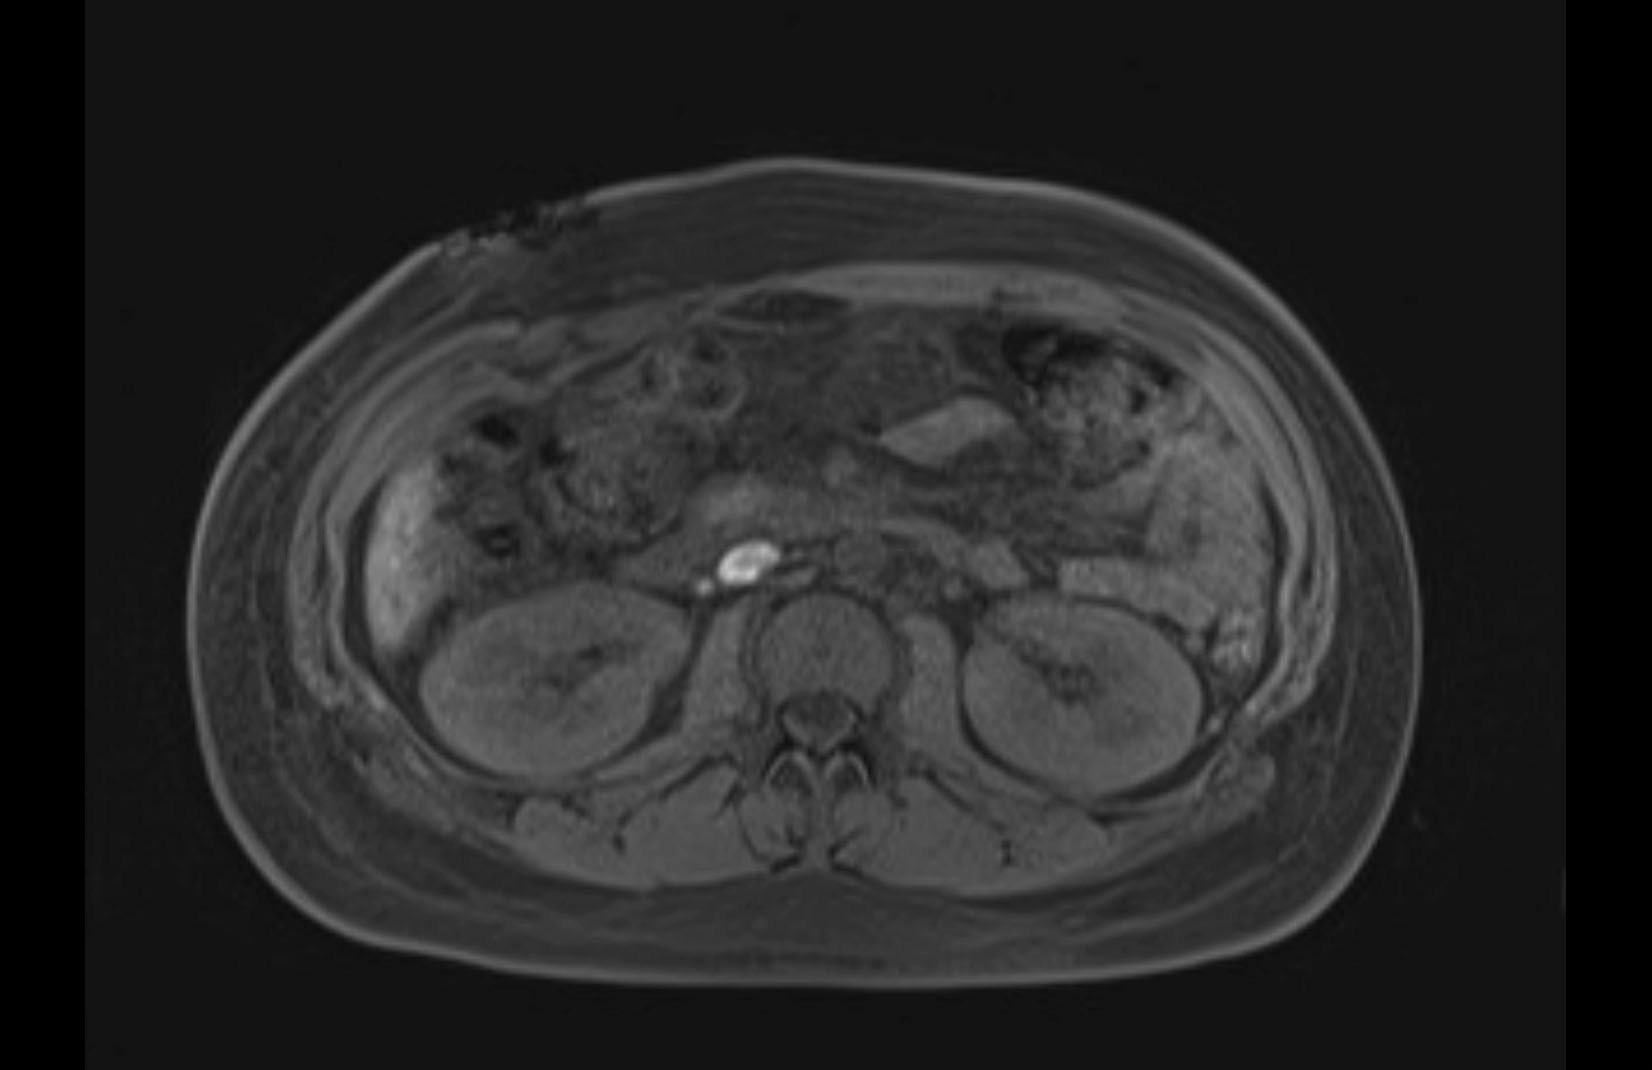

MRI T1

MRI T2